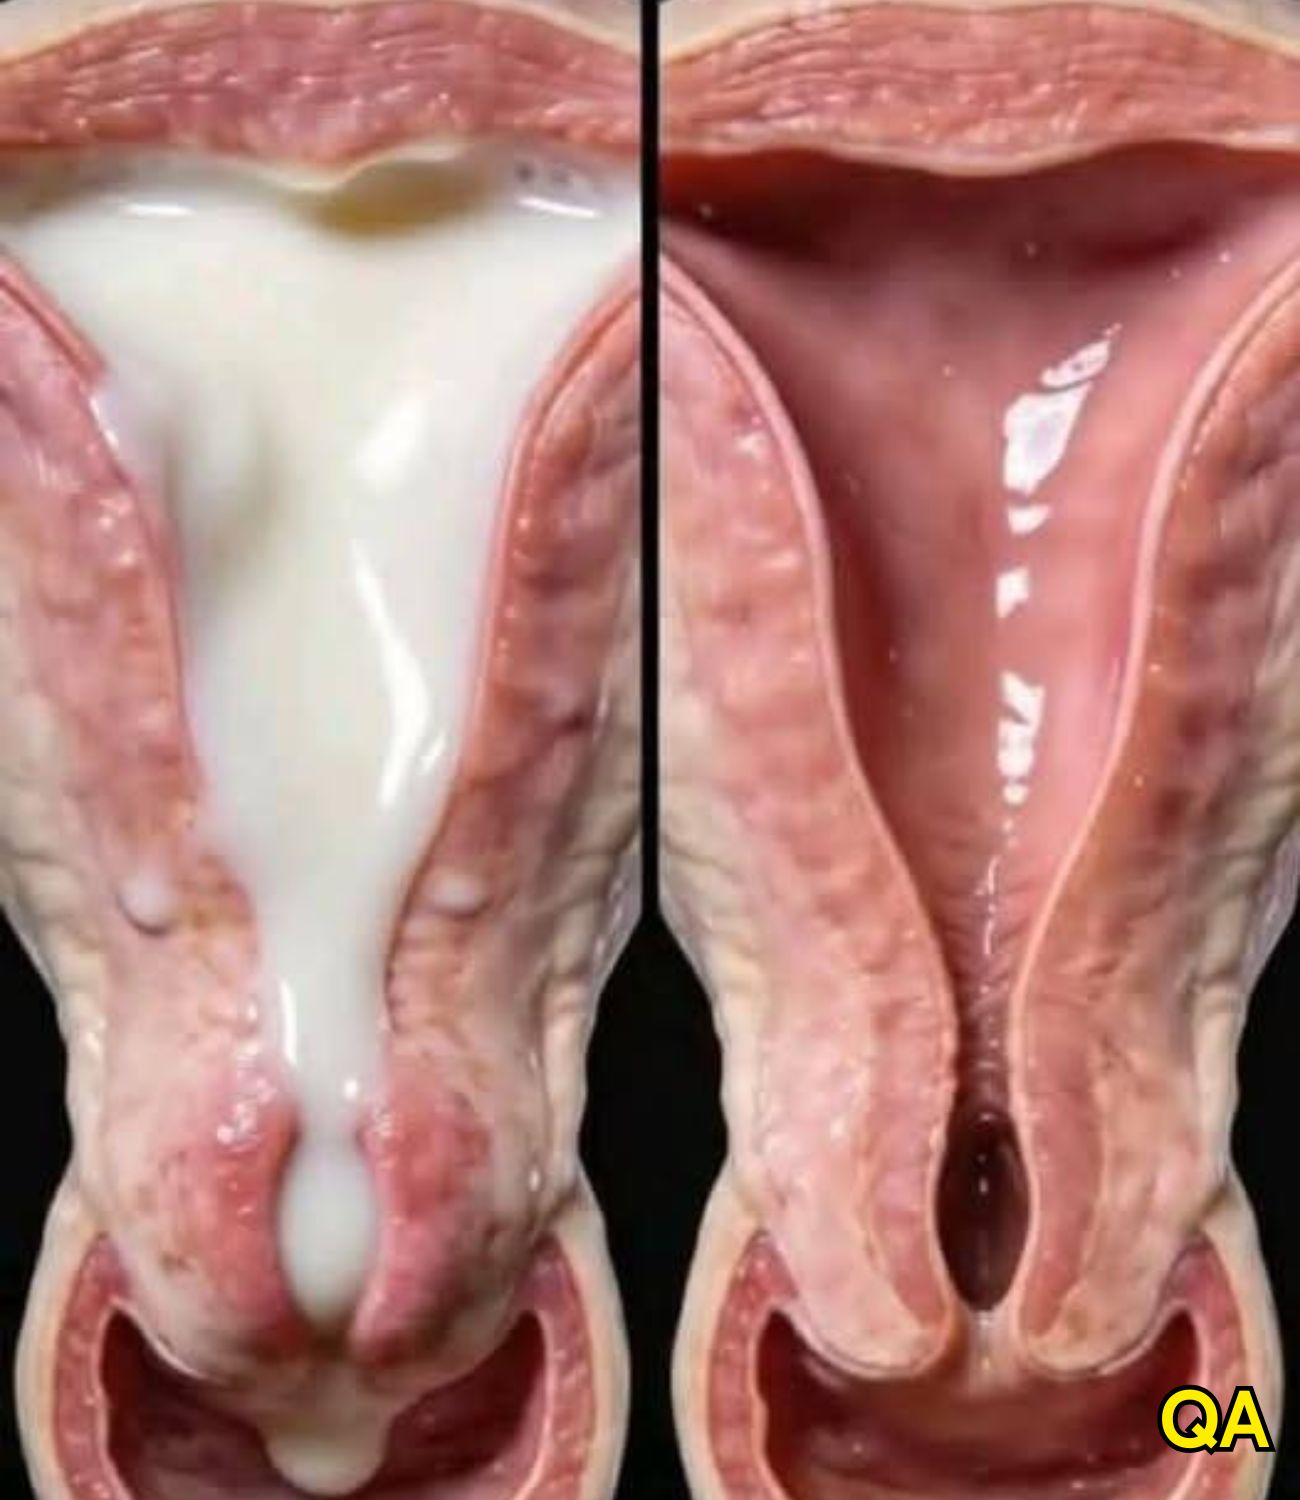

Cervical cancer originates in the cells of the cervix, which is the lower, narrow portion of the uterus that connects to the vagina. Most cervical cancers begin in the transformation zone — the area where the cervix transitions between two types of cells: squamous cells (flat cells lining the ectocervix) and glandular cells (column-shaped cells lining the endocervix).

The two main types of cervical cancer are squamous cell carcinoma, accounting for about 70–90% of all cases, and adenocarcinoma, which develops from the glandular cells. In rare cases, both types may be present simultaneously. Cervical cancer is usually slow-growing, taking years to develop from precancerous lesions into full-blown cancer — which is exactly why early screening is so powerful.

Diagnosis and Treatment

When a Pap smear or HPV test returns an abnormal result, the next step is usually a colposcopy — a procedure in which the doctor examines the cervix under magnification and may take a small tissue sample (biopsy) for laboratory analysis. If precancerous changes are confirmed, treatment options such as LEEP (loop electrosurgical excision procedure), cryotherapy, or cone biopsy can remove the abnormal tissue before it becomes invasive cancer.